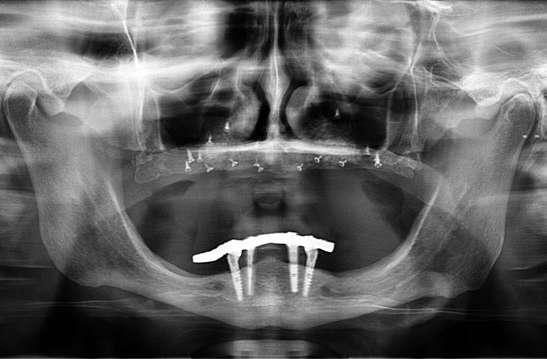

El tiempo de seguimiento fue de 112 meses +/14,85, no observándose ningún fracaso de los implantes estudiados durante este periodo. La media de la pérdida ósea mesial de los implantes estudiados fue de 0,15 mm +/- 0,71 , mientras que la distal fue de 0,31 mm +/- 0,69. Si estudiamos la pérdida ósea crestal separada entre los implantes atornillados y cementados obtenemos que para los implantes cementados la pérdida ósea distal fue de 0,47 mm +/- 0,80 y para los atornillados de 0,15 +/- 0,59 mm siendo las diferencias entre ambos grupos para la pérdida ósea distal estadísticamente significativas (p=0,03). En cambio, para la pérdida ósea mesial, no existieron diferencias estadísticamente significativas para los implantes atornillados y cementados, siendo la media de la pérdida ósea para los cementados de 0,27 +/- 0,83 y para los atornillados de 0,10 +/- 0,60. En la pérdida ósea de conjunto (media de la mesial y distal) para los grupos atornillado y cementado no existieron tampoco diferencias óseas significativas. En las figuras 3-10 se muestran imágenes de dos de los casos incluidos en el estudio.

Figuras 3-6. Imágenes de un caso de prótesis atornillada en molar unitario inferior. Vemos el estado de los tejidos blandos gingivales tras la segunda fase y colocación del transepitelial unitario y la radiografía. En las imágenes inferiores (5 y 6) observamos el caso a los 4 años y 10 años de seguimiento, con estabilidad completa de los tejidos óseos peri-implantarios.

Figuras 7-10. En las dos imágenes superiores (7 y 8) observamos la realización de la prótesis cementada mediante un bioplilar fresado a la altura gingival con la radiografía antes del cementado de la corona. En las imágenes inferiores (9 y 10) vemos la prótesis a los 7 años de seguimiento y a los 9 años transformada en una prótesis atornillada al perderse la pieza anterior al implante y realizarse un puente con el nuevo implante. En este caso, el nivel óseo permanece estable con el paso del tiempo.